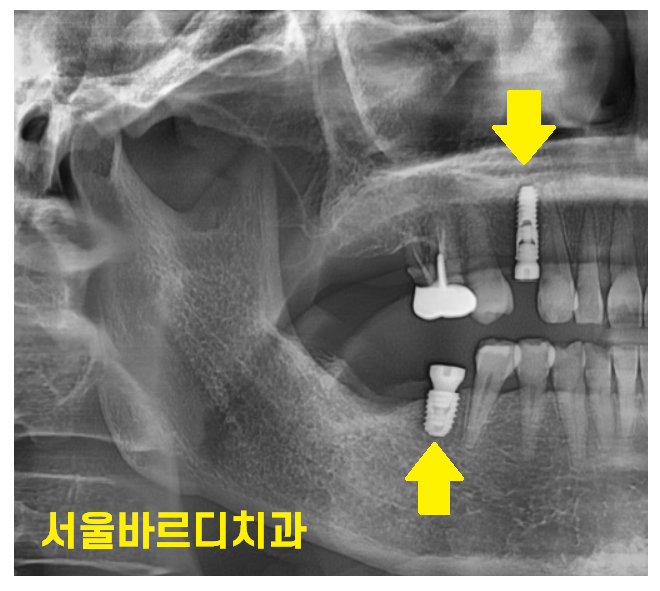

사진으로 직접 인체의 신비..?를 보여드리겠습니다 ㅎㅎ

고덕동 치과를 찾아와주신 한 여성 환자분입니다.

코로나때 치료 시기를 놓치고 몇년만에 고덕동 치과를 방문해주셨다 하셨어요

사진만 봐도 오랜만에 오신 것을

확인할 수가 있었습니다.

발치 자국이 안보인다.

치아 쓰러짐 관찰

240423

문제는 육안으로 볼 때에는

티가 안납니다.

환자분은 그럭저럭 씹을 수도 있어서

문제가 없다 생각하시지만

x-ray를 찍어보면...

이만큼 기울어져있답니다.

적당히 기울어졌으면 신경치료를 하고 치아를 깎는다거나

치아를 살려볼 수 있겠으나

이정도로 치아 쓰러짐 발생하면

뽑고 임플란트를 해야합니다..

240501

환자분도 고덕동 치과에서

치아 쓰러짐 치아 발치 후 임플란트 치료중이세요~